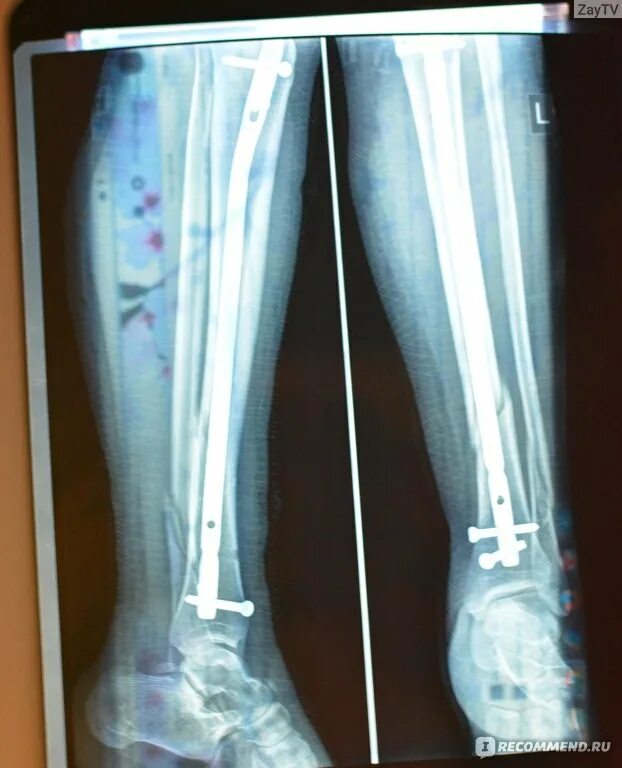

Перелом берцовой кости как разработать